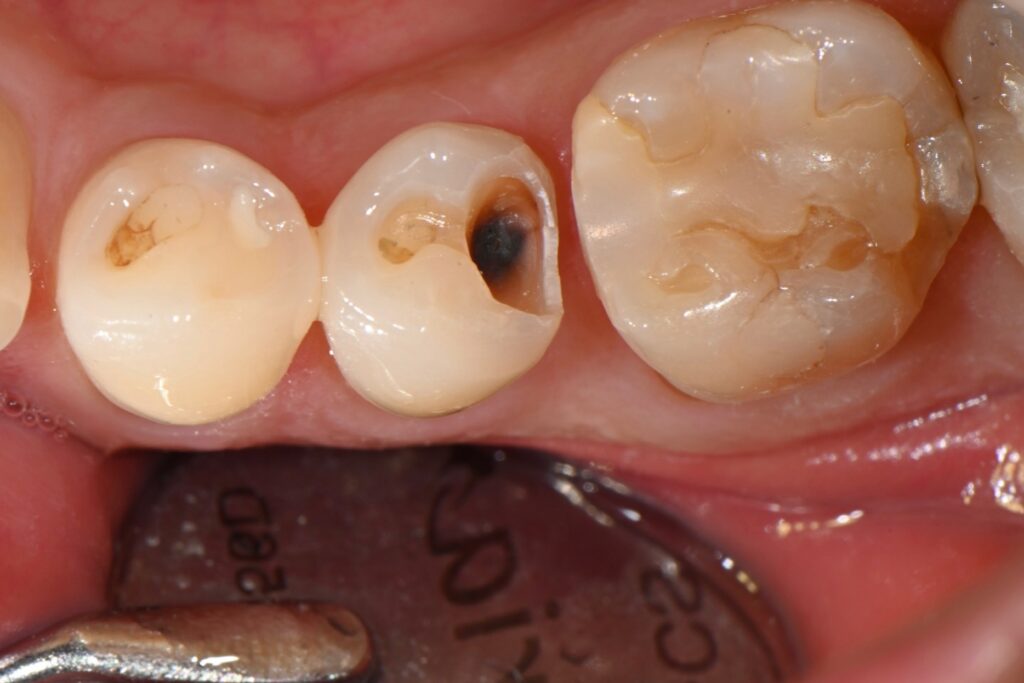

사진을 보시면 인레이와 치아사이에 경계가 보입니다

저 경계부분은 나중에 음식물이 저류하고

세균이 번식할 환경을 만들어 줍니다

그리고 이차충치로 이어지게 되는것이지요

이런식의 문제가 몇년후면 나타나고

재치료가 필요하게 될것입니다

앞서 보여드린 치아를 치료하는 과정입니다

기존의 인레이를 제거하고 나서 충치가 굉장히 깊습니다

이런경우 신경치료의 가능성도 높고

치아삭제가 많은 크라운이나 다른 인레이를 해야 하는데요

하지만 최근 빌드업이라는 치료법으로 치료 하는 과정입니다

역시나 충치가 굉장히 깊습니다

또한 다른 문제가 있습니다

바로 앞에 치아에도 충치가 생겨 있는것이지요

충치균은 세균이기 때문에

그 치아가 충치가 있다면 그 주변에 치아도

같이 충치가 있을 가능성이 높습니다